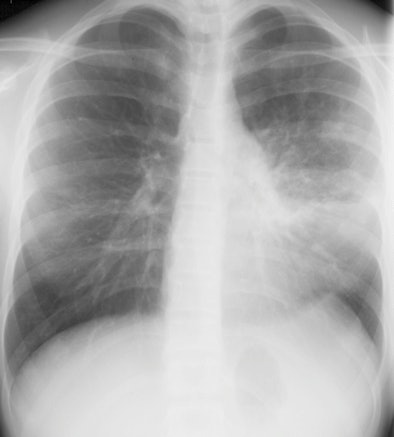

| A 13-year-old girl with pneumonia caused by Mycoplasma pneumoniae. Chest x-ray (above) and a contrast-enhanced 1.5-tesla coronal image (below). The MR image shows patchy parenchymal changes in both lungs. Images courtesy of the Department of Radiology, Turku University Hospital. |